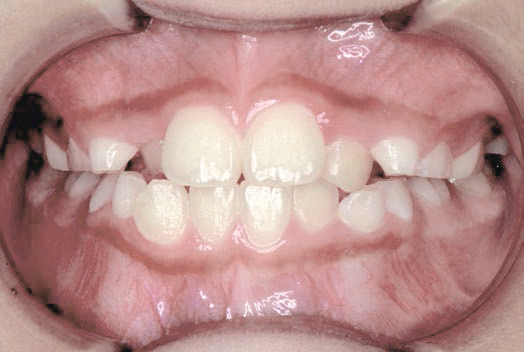

口が閉じない

指しゃぶりのクセがあり、お口を閉じることができません

Aさん (矯正開始時:7歳)

Before

After

舌の位置が低く、上あごの天井が高くて狭い状態でした。鼻がつまりやすく、口をポカンと開けながら呼吸をしていることが確認されました。

治療を終えて

現在まだ治療継続中ですが、装置によって上あごを広げ、下の歯の位置を整える治療中です。お口のトレーニングにより鼻通りがよくなり、鼻呼吸が改善され舌の位置も正しくなりました。指しゃぶりのクセもなくなりました。

主訴・治療内容 指しゃぶりのクセがあり前歯が傾いていることから、お口を閉じることができないというお悩みで来院されました。

治療期間 1年

費用 495,000円(税込)